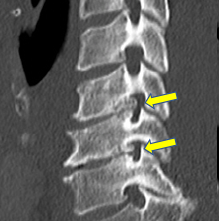

60歳 男性 頚椎症性神経根症

左手のしびれがあり、整形外科で治療を受けられていましたが、改善なく、力も落ちてきたので、来院されました。第5/6頚椎と6/7頚椎の神経が通る椎間孔に骨の突出(骨棘)があり、神経が圧迫されていました。頚部前方から手術を行い、骨棘を取り除き神経の圧迫を解除しました。